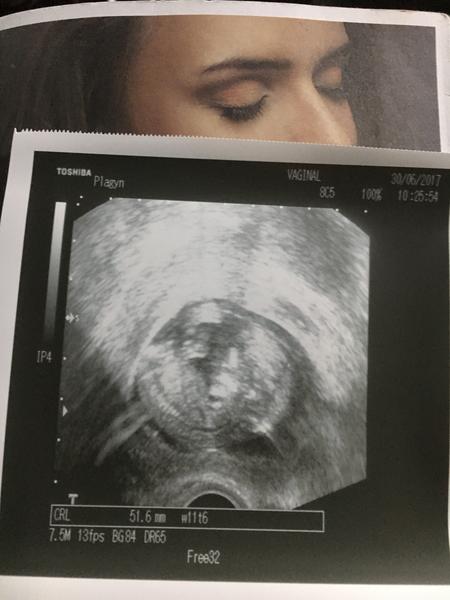

Jinak jak je?Doufám ze jste všechny v pořádku😘já jsem se nakonec rozhodla pro neinvazivni test Harmony, byla jsem v Motole a koncem tydne by mohli být výsledky a budeme vědět i pohlaví 😍tak snad bude vse ok..

@alli005 no právě..jsem v klídku a pak se kolikrát v noci vzbudím a jsem strachy bez sebe..nebo i přes den v práci..pak běžím domu poslechnout ❤..právě že je teď takové hluché období kdy čekáš až mimco začne kopat..jinak test stojí cca 9900,-bez určení pohlaví a 10900 s určením pohlaví..prý je ten test Harmony lepší, udává kolik procent te DNA se jim podařilo zachytit, což je prý důležité..jinak v Motole dělají snad všechny ty testy, vcetně Prenascan..ale líbilo se mi že mě necpali do toho nejdražšího,naopak a byl tam moc příjemný pak doktor..